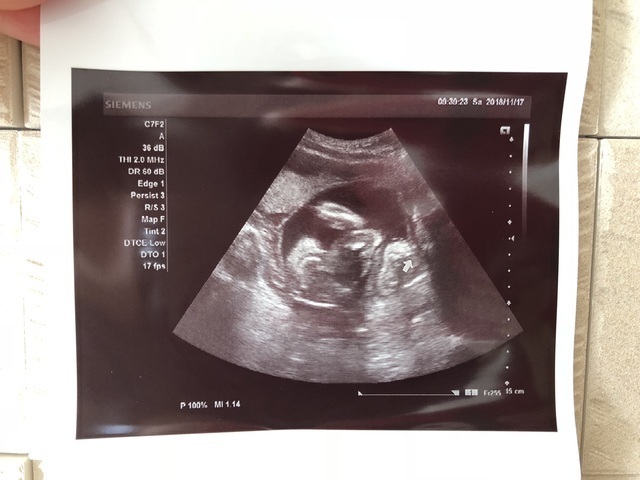

21週0日(21w0d・性別不明)|みちぽぽぽ さん(23歳)

エコー写真撮影時のエピソード:

撮影した時期は20w0d

体調も落ち着き、毎回エコーを見て会えるのが楽しみで週数ピッタリで検診に行ってしまいます!笑

この日はいつも頑なに隠している顔を初めてしっかり見せてくれました♡

アヒル口がパパに似てとっても可愛いのがわかるくらいしっかり成長してて感動...。眠そうに目を擦ったりあくびしたり愛おしさが増しました。胎動もとても激しく、エコーはほとんどブレブレで(笑)助産師さんにもこんな動く子は珍しい、元気だね〜と言われました(笑)